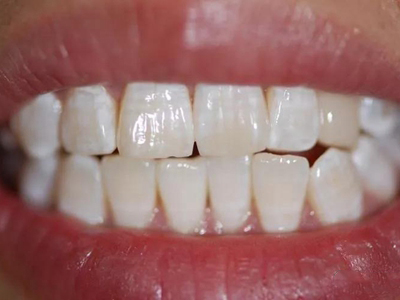

牙釉质发育不全牙齿白斑图

牙釉质发育不全患者可以仅仅出现牙齿色泽和透明度的改变,形成白垩色釉质,即类似于牙齿上有白斑,此时牙冠形态通常较完整。